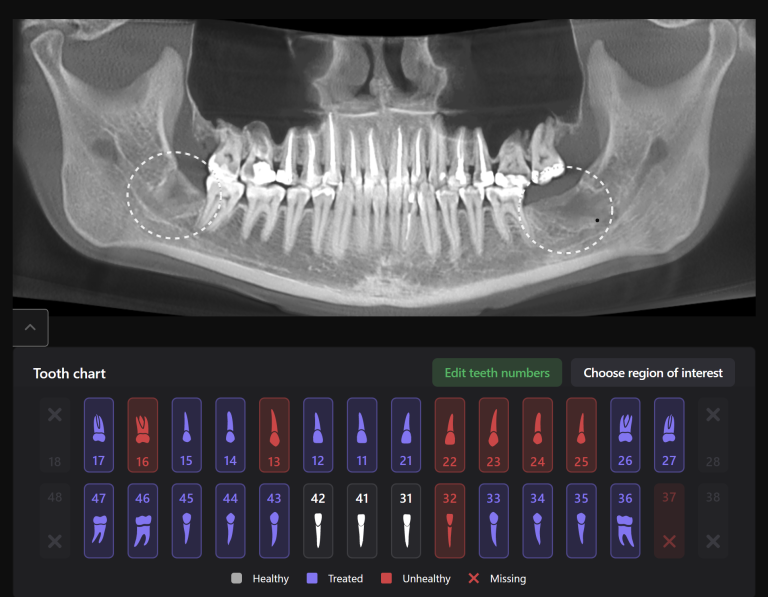

A cross-sectional radiological report created by Diagnocat AI allows the clinician to detect a subgingival calculus and make an accurate prognosis of each tooth before starting any complex treatment, whilst taking into account all of the endodontic, periodontal and functional criteria.